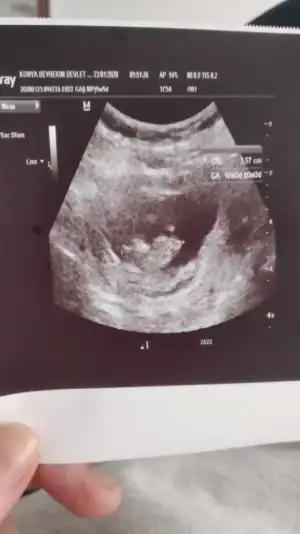

Erkek ve kız için 11 yada 12 hafta usg görüntüsü olmalı açıklamalar asagıda yazıyor 😊 rabbim herkesin gönlüne göre nasip etsin inşallah .. ecmain

[/B]Eki Görüntüle 473828 gordugunuz gibi ust taraftaki simgedende anlasildigi gibi eger cikinti paralel ise kiz

yok 30°lik bir aciyla yukari dogru bakiyorsa %99 oglunuz olacak demektir simdi bi kac ornek resimler daha koyacagim kiziminkide dahil

Eki Görüntüle 473831 simdi burada cikintilara bakin eger bel popo cizgisine paralel ise kiz

yok 30 derecelik bir aciyla yukari bakiyorsa erkek

yabancilarin hepsi biliyor bunu biz neden eksik kalalim gayet bilimsel simdi ellerinde11 12 13 ultrason fotografi olanlar alsin hemen baksin yada koyalim buraya yorumlayalim

Benimkinide değerlendirebilir misiniz ?? Kız mı erkek mi

Eklentiler

• 690363EB-1215-4855-A5FA-F7339D1FD8F5.webp

690363EB-1215-4855-A5FA-F7339D1FD8F5.webp

17,7 KB · Görüntüleme: 34